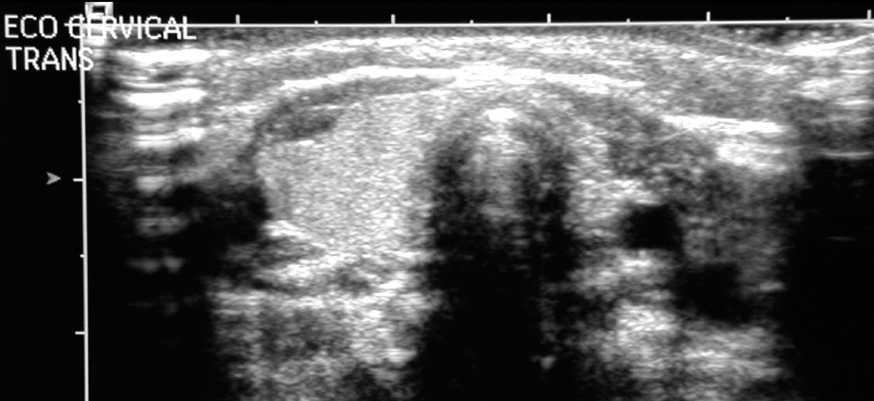

Lactante de 5 meses remitido al Servicio de Endocrinología Pediátrica de nuestro hospital por detectar una función tiroidea alterada (TSH, 32,4 mU/l; tiroxina libre, 0,86 ng/dl) en una analítica realizada a los 4 meses al observarse en el transcurso de una exploración rutinaria la existencia de una hernia umbilical y una fontanela anterior abierta "de tamaño superior al normal". Se trataba de un paciente nacido en nuestro país, fruto de un embarazo escasamente controlado de 33 semanas de gestación, de una madre de 22 años, con padre no conocido. El parto transcurrió sin incidencias y el niño tuvo un peso de nacimiento de 1.620 g, talla de 42 cm, con test de Apgar de 7 al primer minuto y 9 a los 5 minutos. Ingresado hasta el mes de vida por prematuridad y bajo peso al nacimiento, se realizó cribado metabólico neonatal que fue normal. Se desconocían antecedentes familiares de interés. Como antecedentes personales destacaban que el paciente estuvo en centro de acogida desde el alta hospitalaria, fue intervenido de herniorrafia bilateral a los 3 meses de vida y presentó varicela a los 5 meses. La exploración inicial no mostraba hallazgos clínicos de interés, salvo una discreta hernia umbilical, y fontanela anterior abierta normotensa de 3 x 4 cm. La exploración neurológica y el desarrollo psicomotor aparentemente eran adecuados para la edad del paciente. Ante la sospecha de hipotiroidismo congénito se inició tratamiento sustitutivo con L-tiroxina en las dosis habituales y se realizó ecografía tiroidea donde se apreció una importante hipoplasia de lóbulo izquierdo con hipertrofia compensadora del lóbulo contralateral (fig. 1).

Figura 1. Ecografía tiroidea del paciente en la que puede apreciarse una importante hipoplasia del lóbulo izquierdo con hipertrofia compensadora del lóbulo contralateral.